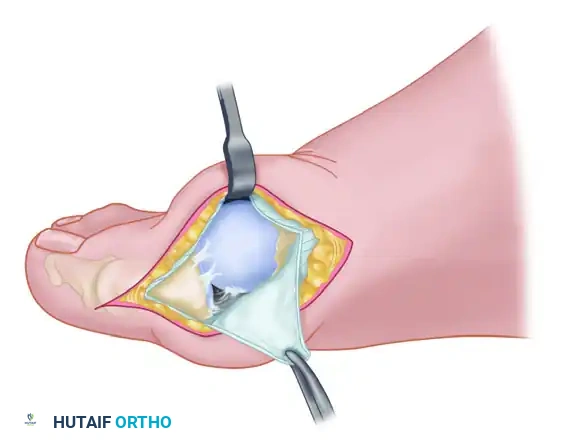

Adductor Tendon and Lateral Capsular Release

The lateral release is the biomechanical heart of the Modified McBride procedure. It mobilizes the tethered lateral structures, allowing the sesamoid apparatus to reduce beneath the metatarsal head.

- Begin the second stage with a dorsal longitudinal incision. Start 2 to 3 mm proximal to the dorsal aspect of the first web space to avoid postoperative web contracture. Extend the incision proximally between the first and second metatarsal heads for 3 to 4 cm.

- This approach provides adequate exposure of the adductor hallucis insertion into the base of the proximal phalanx, the lateral head of the flexor hallucis brevis (FHB) muscle converging on the fibular sesamoid, and the entire lateral capsule.

- Delicate retraction of the skin exposes the dorsal digital branches of the veins, which should be cauterized. Be highly vigilant for the terminal branches of the first dorsal intermetatarsal artery, which may be encountered adjacent to the proper digital branches of the deep peroneal nerve supplying the first web space.

- The main portion of the adductor tendon inserts into the base of the proximal phalanx just plantar to the longitudinal axis of the phalanx. It also possesses a smaller insertion, confluent with the lateral head of the FHB, into the fibular sesamoid.

Surgical Technique Tip: To easily identify the insertion of the adductor hallucis tendon, place a small, pointed, curved hemostat on the dorsolateral base of the proximal phalanx. Slide it firmly plantarward, then lift the hemostat dorsally and laterally. The tip of the instrument will reliably rest in the axilla of the adductor tendon insertion.

- Once the primary insertion is released from the proximal phalanx, grasp the tendon with a hemostat. Apply traction and displace it dorsally and laterally toward the second metatarsal.

- Spread the first and second metatarsal heads using a small Inge retractor or a Weitlaner retractor. Holding the adductor tendon under tension greatly facilitates deep exposure. The lateral head of the FHB, the lateral border of the fibular sesamoid, and the conjoined slip of the adductor tendon will come into clear view.

- Sever all attachments of the adductor into its conjoined insertion with the lateral head of the FHB into the fibular sesamoid. When fully released, traction on the adductor should result in free, independent movement without tethering the fibular sesamoid.

- Next, address the deep transverse intermetatarsal ligament, which lies just plantar to the adductor. Release this ligament carefully.

- Critical Pitfall: Release of the deep transverse metatarsal ligament severely endangers the neurovascular bundle to the first web space, which lies immediately beneath it. Slide a small Freer elevator between the ligament and the neurovascular bundle to protect these structures before incising the ligament. Following this, complete the lateral capsulotomy.